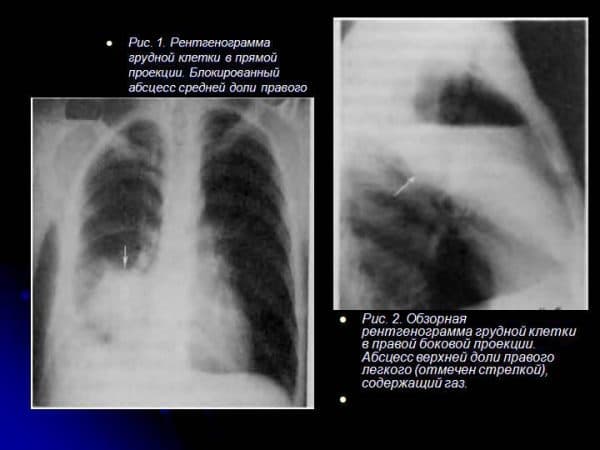

Визначення абсцесу легені по рентгенівському знімку